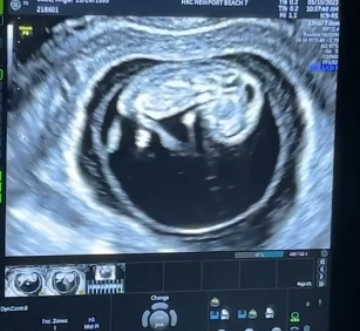

帮助爱妈检查这位年轻有为的博士Lisa是不孕不育的专家,有多年IVF的临床经验。帮助过无数家庭圆梦。十周的宝宝虽然只有40毫米,但是已经长出四肢可以自由活动。爱妈又要迎接孕早期的各种不适和荷尔蒙变化,面对新一轮的挑战,就像升级打怪,但每当看见宝宝的变化都觉得一切都值得,作为爱妈们坚实后盾,可以为她们做哪些事情呢?

十周的宝宝